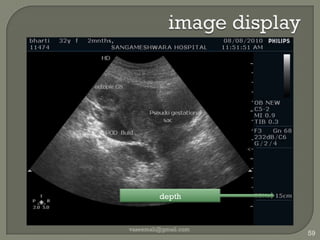

image displayvaseemali@gmail.com59depth